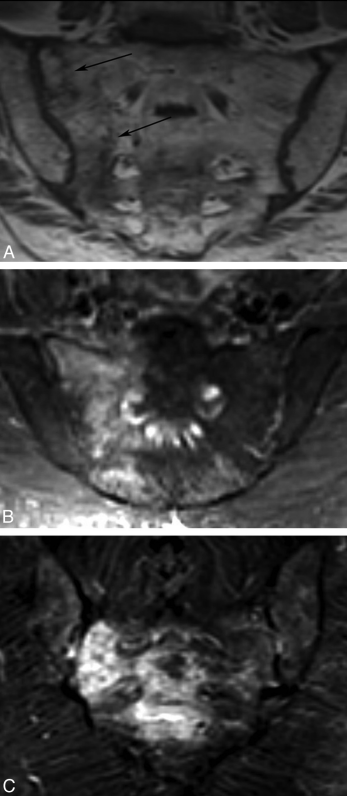

CASE 1

图 1 Case1. T1WI 和 T2WI 显示骶骨左侧份异常信号(蓝色直箭头)、增强扫描明显强化(蓝色弯箭头),T1 压脂高信号(红色直箭头)。

图 2 Case1. Tc-99m MDP 全身骨显像及 SPECT/CT 显像显示骶骨机能不全骨折呈特征性「H」 征。蓝色箭头清晰显示 CT 图像上的骶骨骨折线。